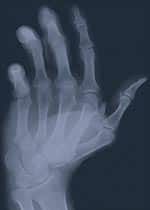

Q: A 53-year-old friend recently visited her doctor, who suggested measuring her bone mineral density (BMD) because she’s going through menopause and is rather petite. She was shocked to learn she had osteoporosis, based on her BMD results. After her diagnosis, my friend added silicon to her supplementation program. What can you tell me about silicon? I’m also going through menopause, but I’m rather tall and not very thin. Am I at risk, and should I get a BMD test? Silicon is a mineral that benefits bone health in many different ways. Silicon in the form of orthosilicic acid (OSA) is necessary for optimal production of type 1 collagen, the kind found in connective tissue such as bone and skin. Silicon also is a critical agent in the body’s glycosaminoglycan network, which utilizes compounds such as hyaluronic acid and chondroitin sulfate in the cartilage, bone, and skin. I believe that supplementing with silicon, in the form of choline-stabilized orthosilicic acid (ch-OSA), is a prudent course for your friend. I will explain why in more detail after discussing osteoporosis and bone mineral density. Assessing Your Risk for OsteoporosisNumerous factors can contribute to the development of osteoporosis. Heredity is very important, especially a history of osteoporosis on your mother’s side of the family. If your mother suffered a hip fracture, you are at greater risk for developing osteoporosis. Early onset of menopause prolongs the period without ovarian hormones, which also increases risk for osteoporosis. In addition, low body weight, shorter stature, excessive alcohol consumption, smoking, an unbalanced diet, and taking high doses of cortisone over an extended period all increase a person’s risk. The one-minute self-assessment test shown below can help you gauge your risk for developing osteoporosis. If your score is less than 13, you are at low risk for osteoporosis. Continue to practice habits that support bone health, since it is easier to prevent than to treat a disease. If your score is 13 or above, you are at risk for osteoporosis or you may already be affected. Talk to your doctor and ask for a BMD test. Understanding Bone Mineral DensityBone mineral density (BMD) assessment seeks to determine whether a person has osteoporosis or osteopenia (low bone mass associated with increased risk for osteoporosis). The World Health Organization defines osteopenia as a condition in which a woman’s BMD is at least one standard deviation, but not more than 2.5 standard deviations, below the average BMD of a healthy young woman at peak bone density. This correlates with a BMD T-score of -1 to -2.5. Women who have a BMD of more than 2.5 standard deviations below the young adult reference range, or a BMD T-score of less than -2.5, are considered to have osteoporosis. As a general rule, a woman’s risk of fracture doubles for every standard deviation below the young adult reference range. For example, if a patient’s T-score is -2, she has a four times greater risk of suffering a fracture than a young woman at peak bone density. Minerals make up only about two thirds of bone mass. The remaining third comprises living cells and type 1 collagen fibers that form a matrix often referred to as “ground substance,” which holds the mineralized deposits in place. While BMD testing is useful for assessing the mineral content of bones, it does not assess the quality of the connective tissue matrix supporting those minerals. Specialists now think that the quality of a bone’s collagen-based matrix structure is even more critical in preventing fractures than is the degree of mineralization. Unfortunately, there is no widely available test to directly and non-invasively measure the health of a person’s ground substance. While the BMD test does not provide a complete picture of bone health, it remains the test best able to help gauge a person’s risk of fracture. BMD test results can be used in concert with specific markers for bone turnover in the serum and urine to develop a more complete assessment of osteoporosis risk. The Importance of SiliconWith growing recognition of the importance of nourishing and supporting the living ground substance of bone, silicon is now widely viewed as an essential nutrient for healthy bone metabolism. Other critical nutrients for the bones include vitamins D, K, C, and B6, the minerals calcium, magnesium, and zinc, and the trace elements copper, manganese, and boron. Throughout life, the body continuously breaks down and rebuilds bone structure in a process known as remodeling. During remodeling, osteoclast cells control the breakdown and resorption of existing bone mass, and osteoblast cells control the formation of new bone mass. The biological process of bone formation and resorption is often referred to as bone turnover. A woman’s bone mass generally remains fairly constant until the start of menopause, when bone resorption typically begins to exceed bone formation. Bone resorption in women accelerates immediately after the start of menopause, and an estimated 1-5% of bone density is lost during the first six to eight years of menopause. Research suggests that silicon helps build and maintain bone in different ways, including regulating bone mineralization, helping to trigger the deposition of calcium and phosphate, reducing the number of osteoclast cells available to destroy existing bone, and increasing the number of osteoblast cells available to reform new bone. Orthosilicic acid, or OSA, is the key silicon compound. Physiological concentrations of OSA were recently found to stimulate type 1 collagen synthesis in human osteoblast-like cells,1 and animal studies have noted improvements in skin collagen after supplementation with choline-stabilized orthosilicic acid (ch-OSA).2 The creation of new osteoblast cells is vital to proper bone remodeling, because these cells are used only once by the body. Osteoblast cells become encased in the collagen matrix they emit once the matrix becomes calcified; once encased, they no longer generate new collagen. A recent study indicates that higher dietary silicon intake is associated with greater BMD in both men and premenopausal women.3 Another newly released study found that ch-OSA partially prevented femoral bone loss in the ovariectomy rat model, a standard model for investigating osteoporosis prevention and intervention therapies.4 Healthy Bones, Healthy SkinCholine-stabilized orthosilicic acid may also help restore elasticity and suppleness to sun-damaged skin, as well as strengthen brittle hair and nails. Scientists at the Free University of Brussels (Belgium) conducted a 20-week double-blind study involving 50 women, aged 40 to 65, who had clear signs of sun-damaged or prematurely aged skin. Half of the subjects received 10 mg of biologically active silicon in the form of ch-OSA, while the other half were given a placebo. Compared to the placebo group, the ch-OSA group experienced significant improvements, including shallower micro-wrinkles (up to 30% better), improved skin elasticity (55% better), and a significant reduction in brittleness of hair and nails.5 This improvement in skin parameters produced by ch-OSA could be a result of the regeneration of old collagen fibers or the synthesis of new ones. By supporting the synthesis of glycosaminoglycans, silicon plays a critical role in supporting the building blocks found in the connective tissues and skin. Animal studies have shown that silicon deficiencies cause collagen abnormalities, including bone deformities.6 Cell culture studies are helping us understand some of the roles of silicon-dependent enzymes,1,6 and observational and interventional trials of animals and humans have shown favorable correlations between silicon consumption and the health of bone and connective tissue.2,3,5,6 While silicon is the second most abundant mineral in the Earth’s crust, little of it exists in a form that humans can readily absorb and utilize. In fact, dietary silicon compounds must to be solubilized by stomach acid into orthosilicic acid (OSA) before they can be absorbed in the gastrointestinal tract. Highly dilute amounts of OSA are found in spring water and beer, but most foods contain large polymers, or long chains, of OSA called silicates. Choline is important for maintaining the structural integrity of cellular membranes, and dietary sources of choline are needed to maintain optimal health. Choline in ch-OSA is believed to have a synergistic effect with OSA, since both compounds are important for cell growth. When choosing a silicon dietary supplement, consumers should seek one containing choline-stabilized orthosilicic acid (ch-OSA) to receive maximum benefits. Johan Briké, MD, received his medical degree from the University of Louvain, Belgium, and is a licensed general practitioner. Dr. Briké is chief editor of the journal Ahead in Neurology. | |